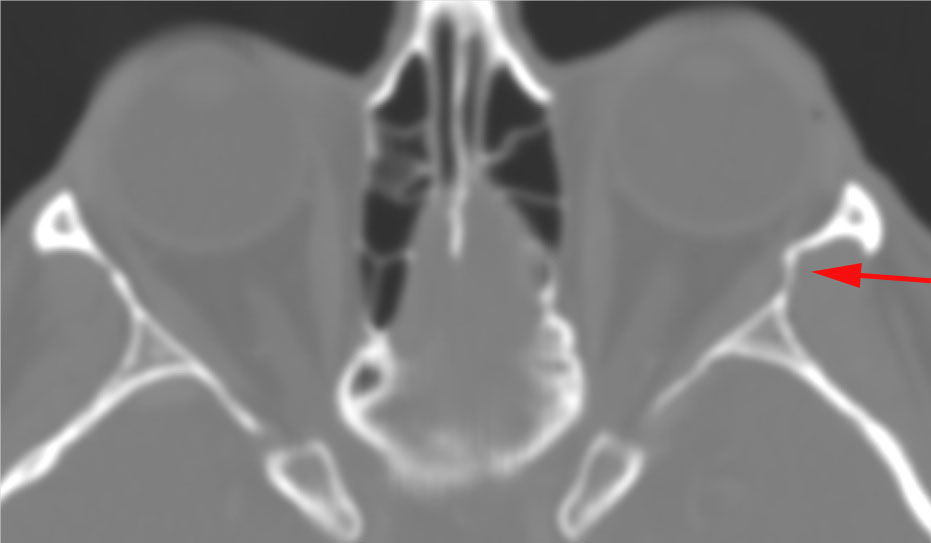

The zygomatic arch is fractured. [Yes/No]

There is entrapment of the muscles of mastication by fractures of the coronoid process and/or zygomatic arch. [Yes/No]